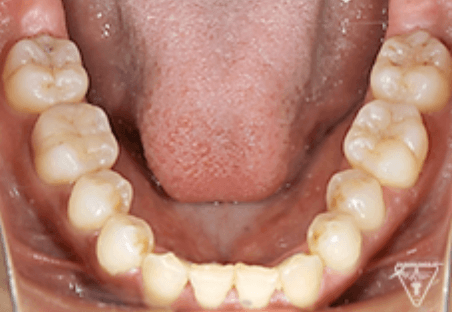

治療過程①

治療過程②

治療過程③

治療後